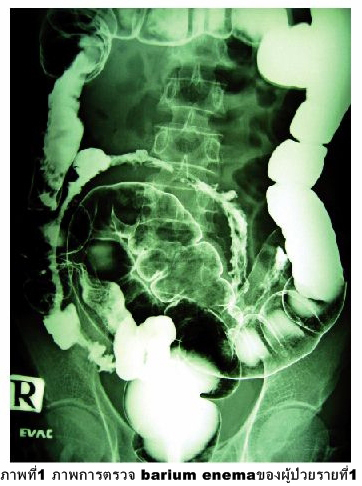

ชายอายุ 39 ปี ภูมิลำเนายโสธร มาด้วยถ่ายเหลวเรื้อรัง และน้ำหนักตัวลดลง 4 กก.ใน 1 เดือน ไม่มีไข้. การตรวจ barium enema ปรากฏผลดังภาพที่ 1. การตรวจร่างกายพบว่ามีรอยแผลเป็นงูสวัดที่หน้าอกด้านซ้าย.

1. ผลการตรวจ barium enema พบว่าเงาโพรงลำไส้เล็กส่วน ilium แคบและผนังไม่เรียบ ลักษณะเข้าได้กับ ileitis เมื่อพิจารณาควบคู่กับอาการถ่ายเหลวเรื้อรัง น่าจะให้การวินิจฉัยเบื้องต้นว่าเป็น ileitis เรื้องรัง. สาเหตุที่อาจเป็นไปได้ เช่น วัณโรคลำไส้, Crohn ' s disease, inflammatory bowel disease, irritable bowel syndrome เป็นต้น. แต่เนื่องจากผู้ป่วยรายนี้อยู่ในวัยเจริญพันธุ์ และมีรอยแผลเป็น งูสวัดที่หน้าอกด้านซ้ายทำให้ต้องสงสัยว่าผู้ป่วยมี ภาวะภูมิคุ้มกันบกพร่องหรือไม่ จึงได้ซักประวัติเพิ่มเติมและพบว่าผู้ป่วยโสด แต่มีเพศสัมพันธ์แบบไม่ได้ป้องกันมาหลายปี. ผลการตรวจ anti-HIV แอนติบอดีเป็นบวก. สาเหตุที่น่าสงสัยมากที่สุดในรายนี้จึงเป็น ileitis เรื้อรังจากวัณโรคลำไส้.